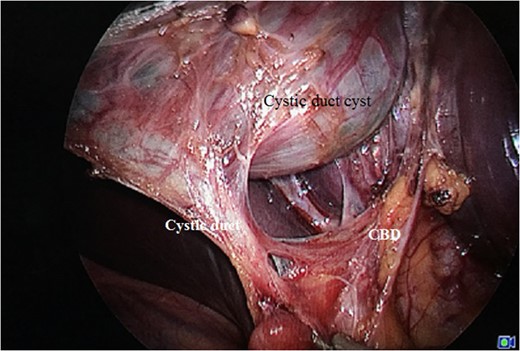

Cyst seen along with the cystic duct stalk and the arterial twig supplying the cystic duct.

The management of Type VI choledochal cyst is guided by its morphology [1–7]. The surgery recommended for Type VI choledochal cyst with a narrow-based cystic duct stalk is simple cholecystectomy with cyst excision. Wide-based cystic duct with proximity to the CBD warrants a CBD excision along with the above procedure and bilio-enteric reconstruction. Most of the authors reported in the literature have described the surgery by open or laparoscopic converted to open route. We did a complete laparoscopic mobilisation and cyst excision with cholecystectomy in the present case. Detailed assessment of the histology is important to detect any neoplastic changes. In patients undergoing CBD excision as a part of the procedure, evaluation of the margins for neoplasia is important. Proved malignancy of the cyst with CBD or GB warrants a definitive procedure in the form of Whipple's operation or radical cholecystectomy, respectively.